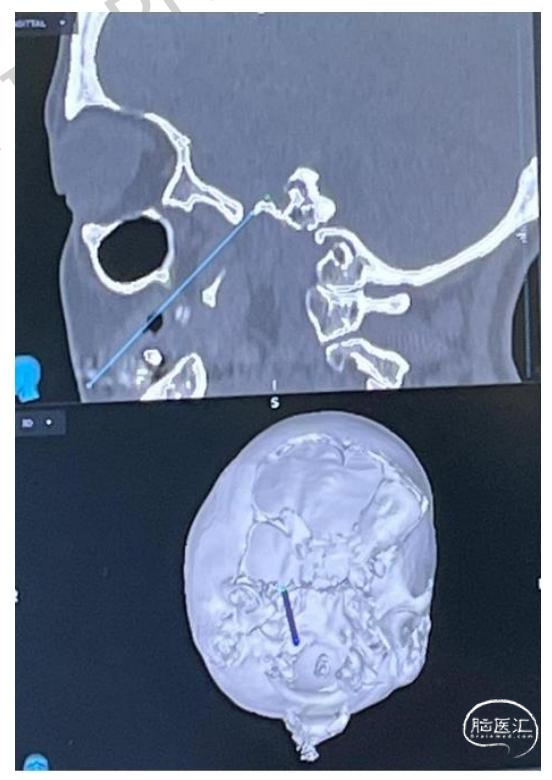

1.术前规划:术前1日,患者接受头颅及面颅薄层CT扫描,数据集导入StealthStation S8系统,术前完成靶向卵圆孔的穿刺针道设计(图1)。术者可识别解剖变异,并在必要时调整进针点,进针点可能偏离经典Hartel入路。

图1:经皮球囊压迫术的术前神经导航规划头颅CT图像,清晰显示靶向卵圆孔的预设穿刺针道(蓝线);三维表面重建可确认皮肤进针点相对于面部标志的位置,从而优化穿刺轨迹、避免骨质碰撞。

3.穿刺点定位与进针:采用电磁神经导航确认皮肤进针点与预设穿刺路径,同时以C臂透视实时确认穿刺针推进位置,并可通过造影剂验证球囊充盈是否到位。进针点通常位于患侧口角外侧约2.5 cm处(图2)。穿刺针初始推进时,将非优势手手指置入口腔,避免损伤口腔黏膜。所用穿刺针为KCA 11/15-10型穿刺针,配备双针芯、斜形与套管针针尖、11号球囊、球囊固定器、带旋塞的3 ml注射器及符合人体工学的侧翼。在透视引导下,沿瞳孔中线平面向岩骨嵴与斜坡交点推进穿刺针,侧位透视下以内耳道对齐确认方位(图3)。针尖触及骨质后,撤出针芯,将Axiem电磁传感器置入套管内,比对实际轨迹与术前导航预设路径的精准度(图4)。此阶段可出现反射性下颌抽搐,偶见脑脊液流出,无需特殊处理。